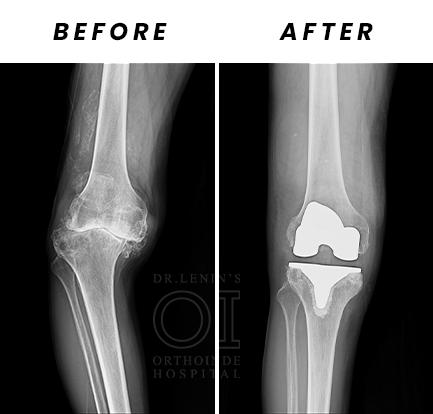

If the procedure is a simple replacement of the total knee, the surgery is called Primary Knee Replacement. Primary Knee Replacement surgery is also referred as Total Knee Arthroplasty or TKA in short

In most of the primary knee replacement procedures, the joint surfaces at the end of thigh bone and the top of the shin bone are replaced. Sometimes the under surface of the kneecap (called the patella) is replaced with specialized plastic domes. But this decision is taken by the surgeon after studying individual cases. The orthopaedic surgeon always prefers to retain the natural patella. But if situation warrants then patella is replaced. At times, this decision is made during the surgery also.